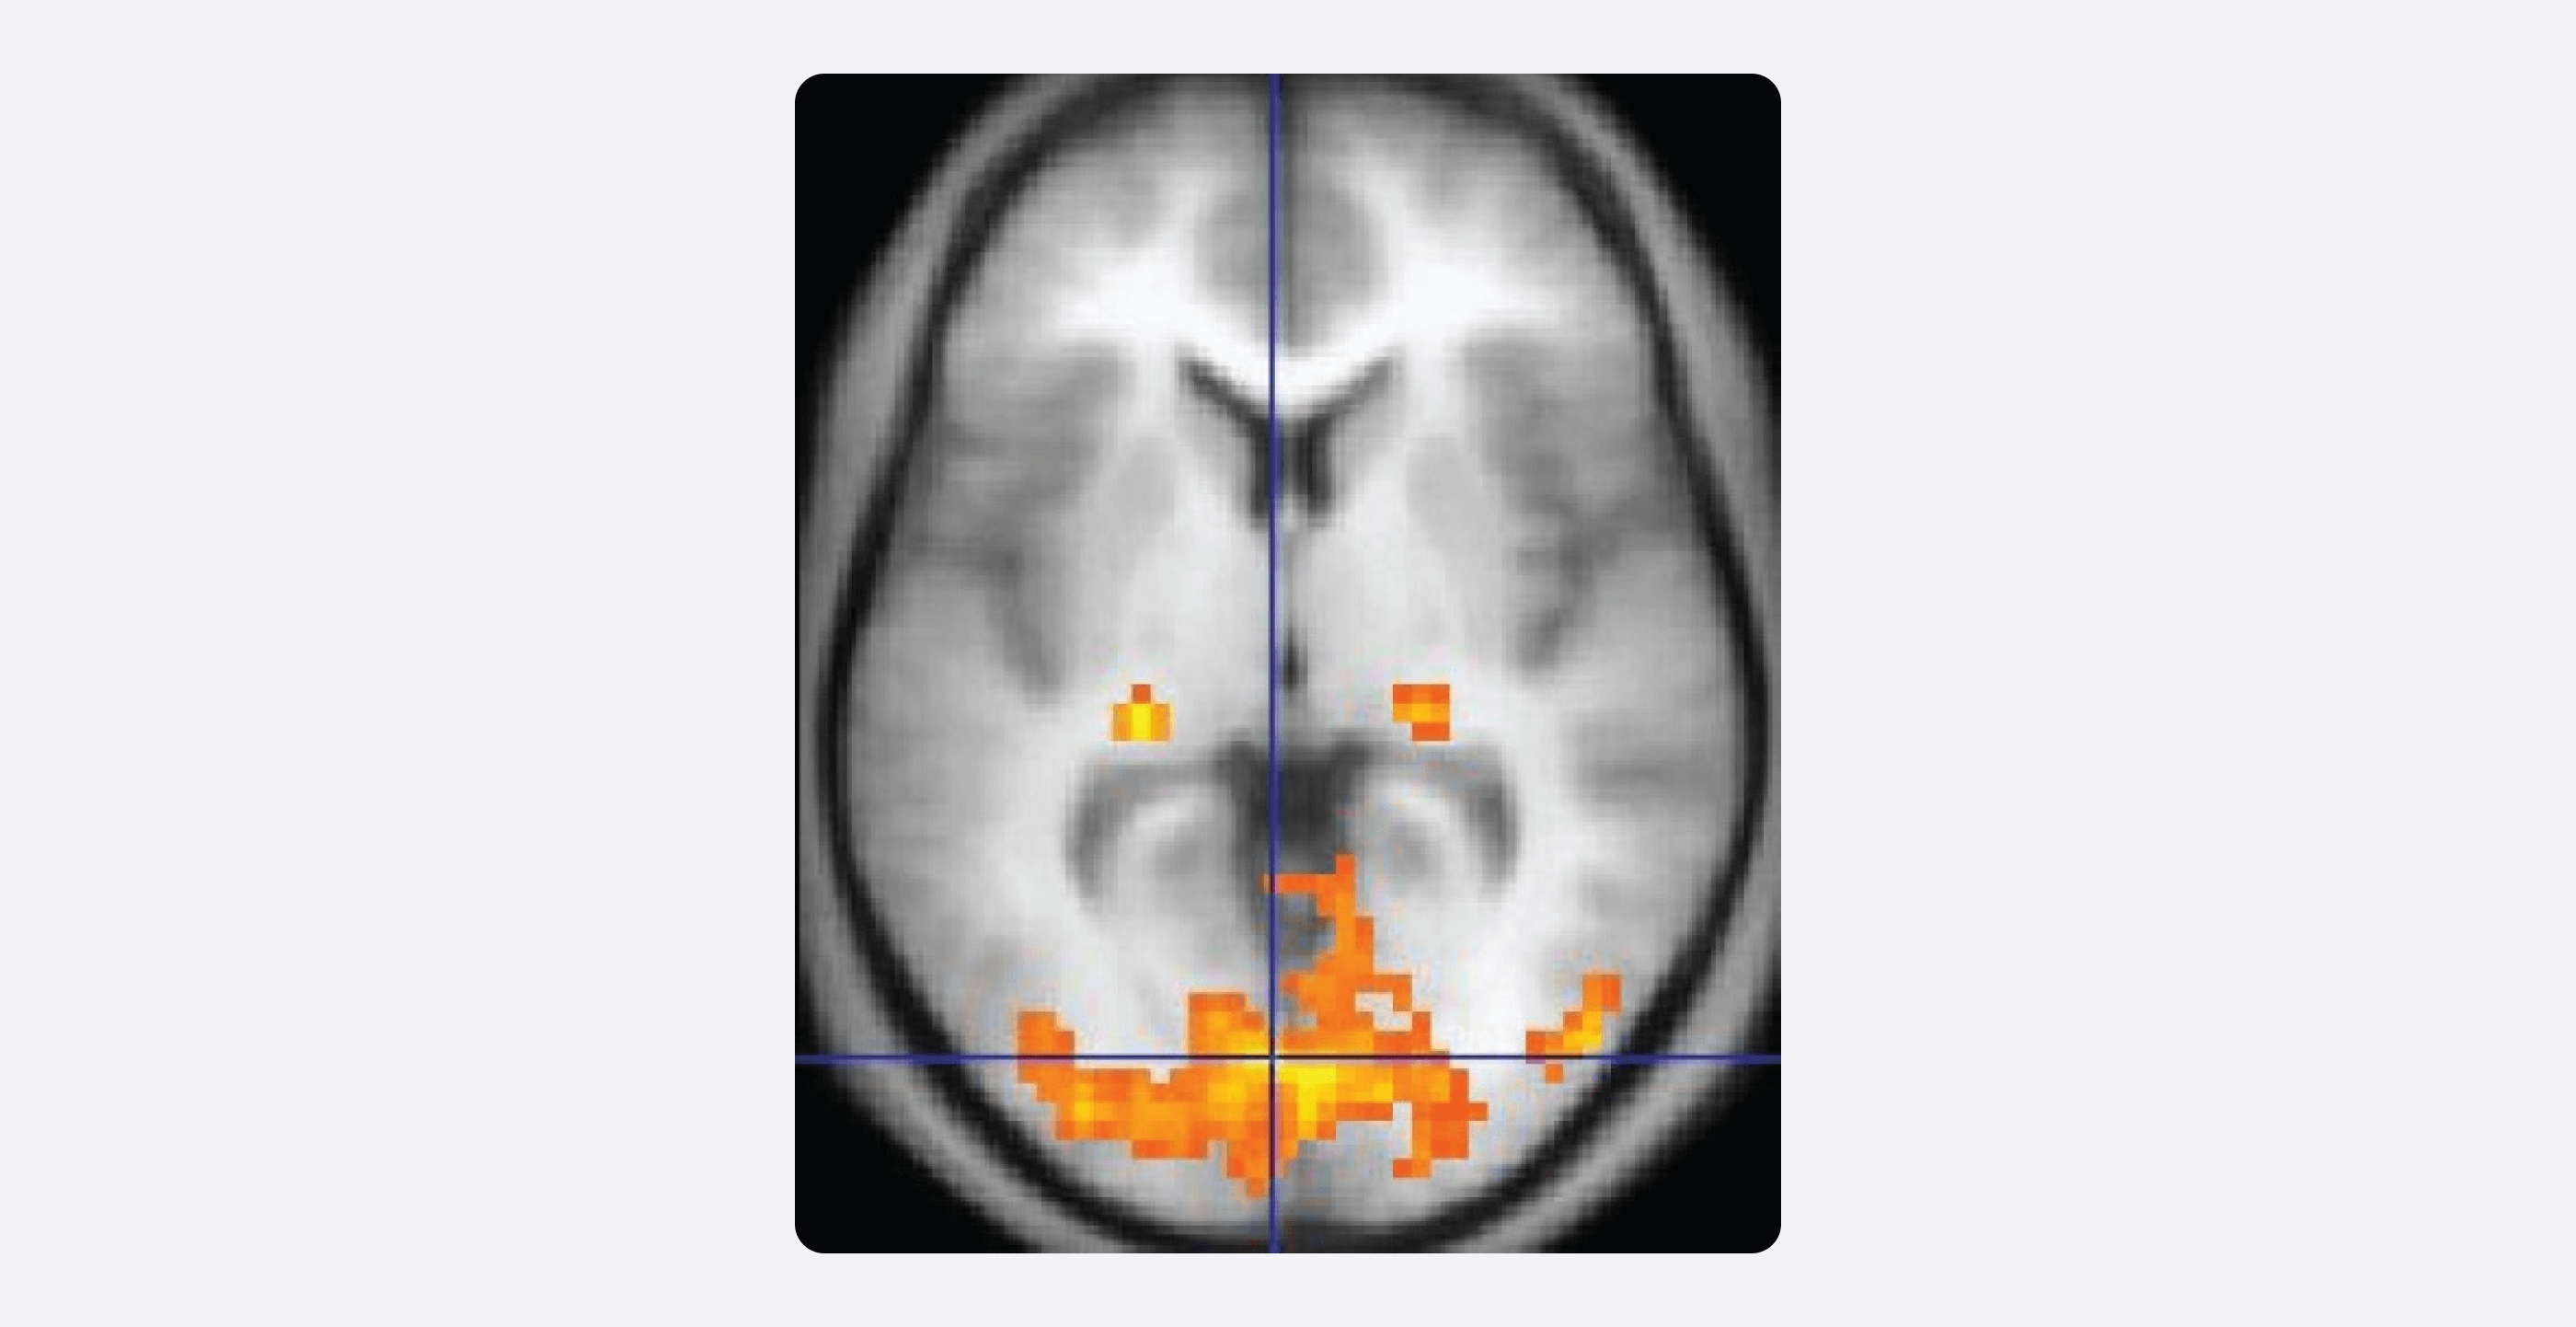

Пример изображения, полученного с помощью фМРТ (из учебника OpenStax Anatomy and Physiology). Подсвеченные области — это зоны повышенной активности.